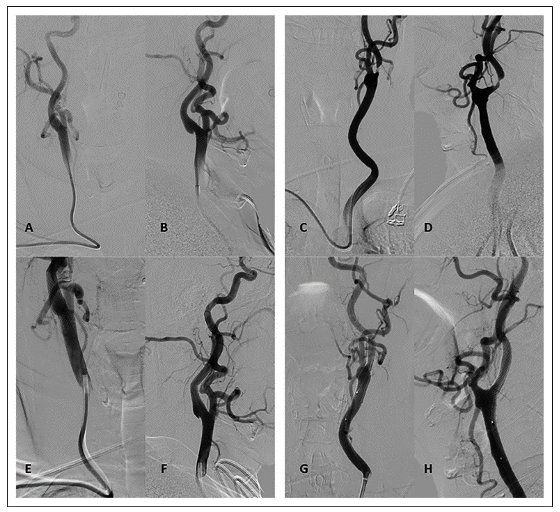

在硬的150 cm 0.035in 45° J形导丝(Terumo Radifocus, Louvain, Belgium)上,缓慢地推送一根内径0.078in (Envoy, Codman Neuro, Raynham, MA, USA)长为90cm的7F Simmons 2导管。首先在降主动脉系统地进行导管头端成形。如果不成功,可在主动脉瓣上方成形,有时也可在导管不成形的情况下直接对血管进行导管置入。在每次球囊血管成形术(Viatrac 14 plus, Abbot Vascular, Santa Clara, CA, USA)过程中,通过导引导管进行近端抽吸,使用60ml注射器预防远端栓塞。术中未使用远端栓塞保护装置。右侧和左侧颈动脉狭窄病例如图2所示。

图2. DSA正侧位显示右侧(A和B)和左侧(C和D)颈内动脉狭窄。

来自7F Simmons 2导管造影CAS后右侧(E和F)和左侧(G和H)颈内动脉。